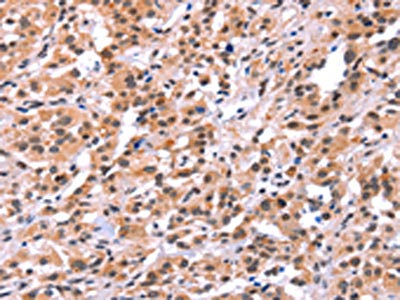

The image on the left is immunohistochemistry of paraffin-embedded Human colon cancer tissue using CSB-PA993829(MYF5 Antibody) at dilution 1/15, on the right is treated with synthetic peptide. (Original magnification: x200)